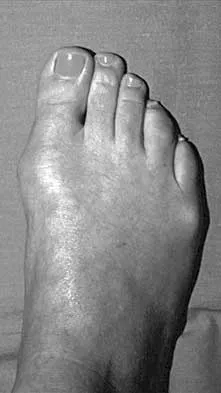

A 28-year-old woman has a moderate hallux valgus deformity and a prominence of the medial eminence. She can participate in all activities and reports that she could wear 3-inch heels in the past, but she now notes medial eminence pain even while wearing a soft leather flat shoe with a cushioned sole. She requests recommendations regarding surgical correction. Examination reveals a 1-2 intermetatarsal angle of 10 degrees. A clinical photograph and radiograph are shown in Figures 13a and 13b. What is the best course of action?

Explanation